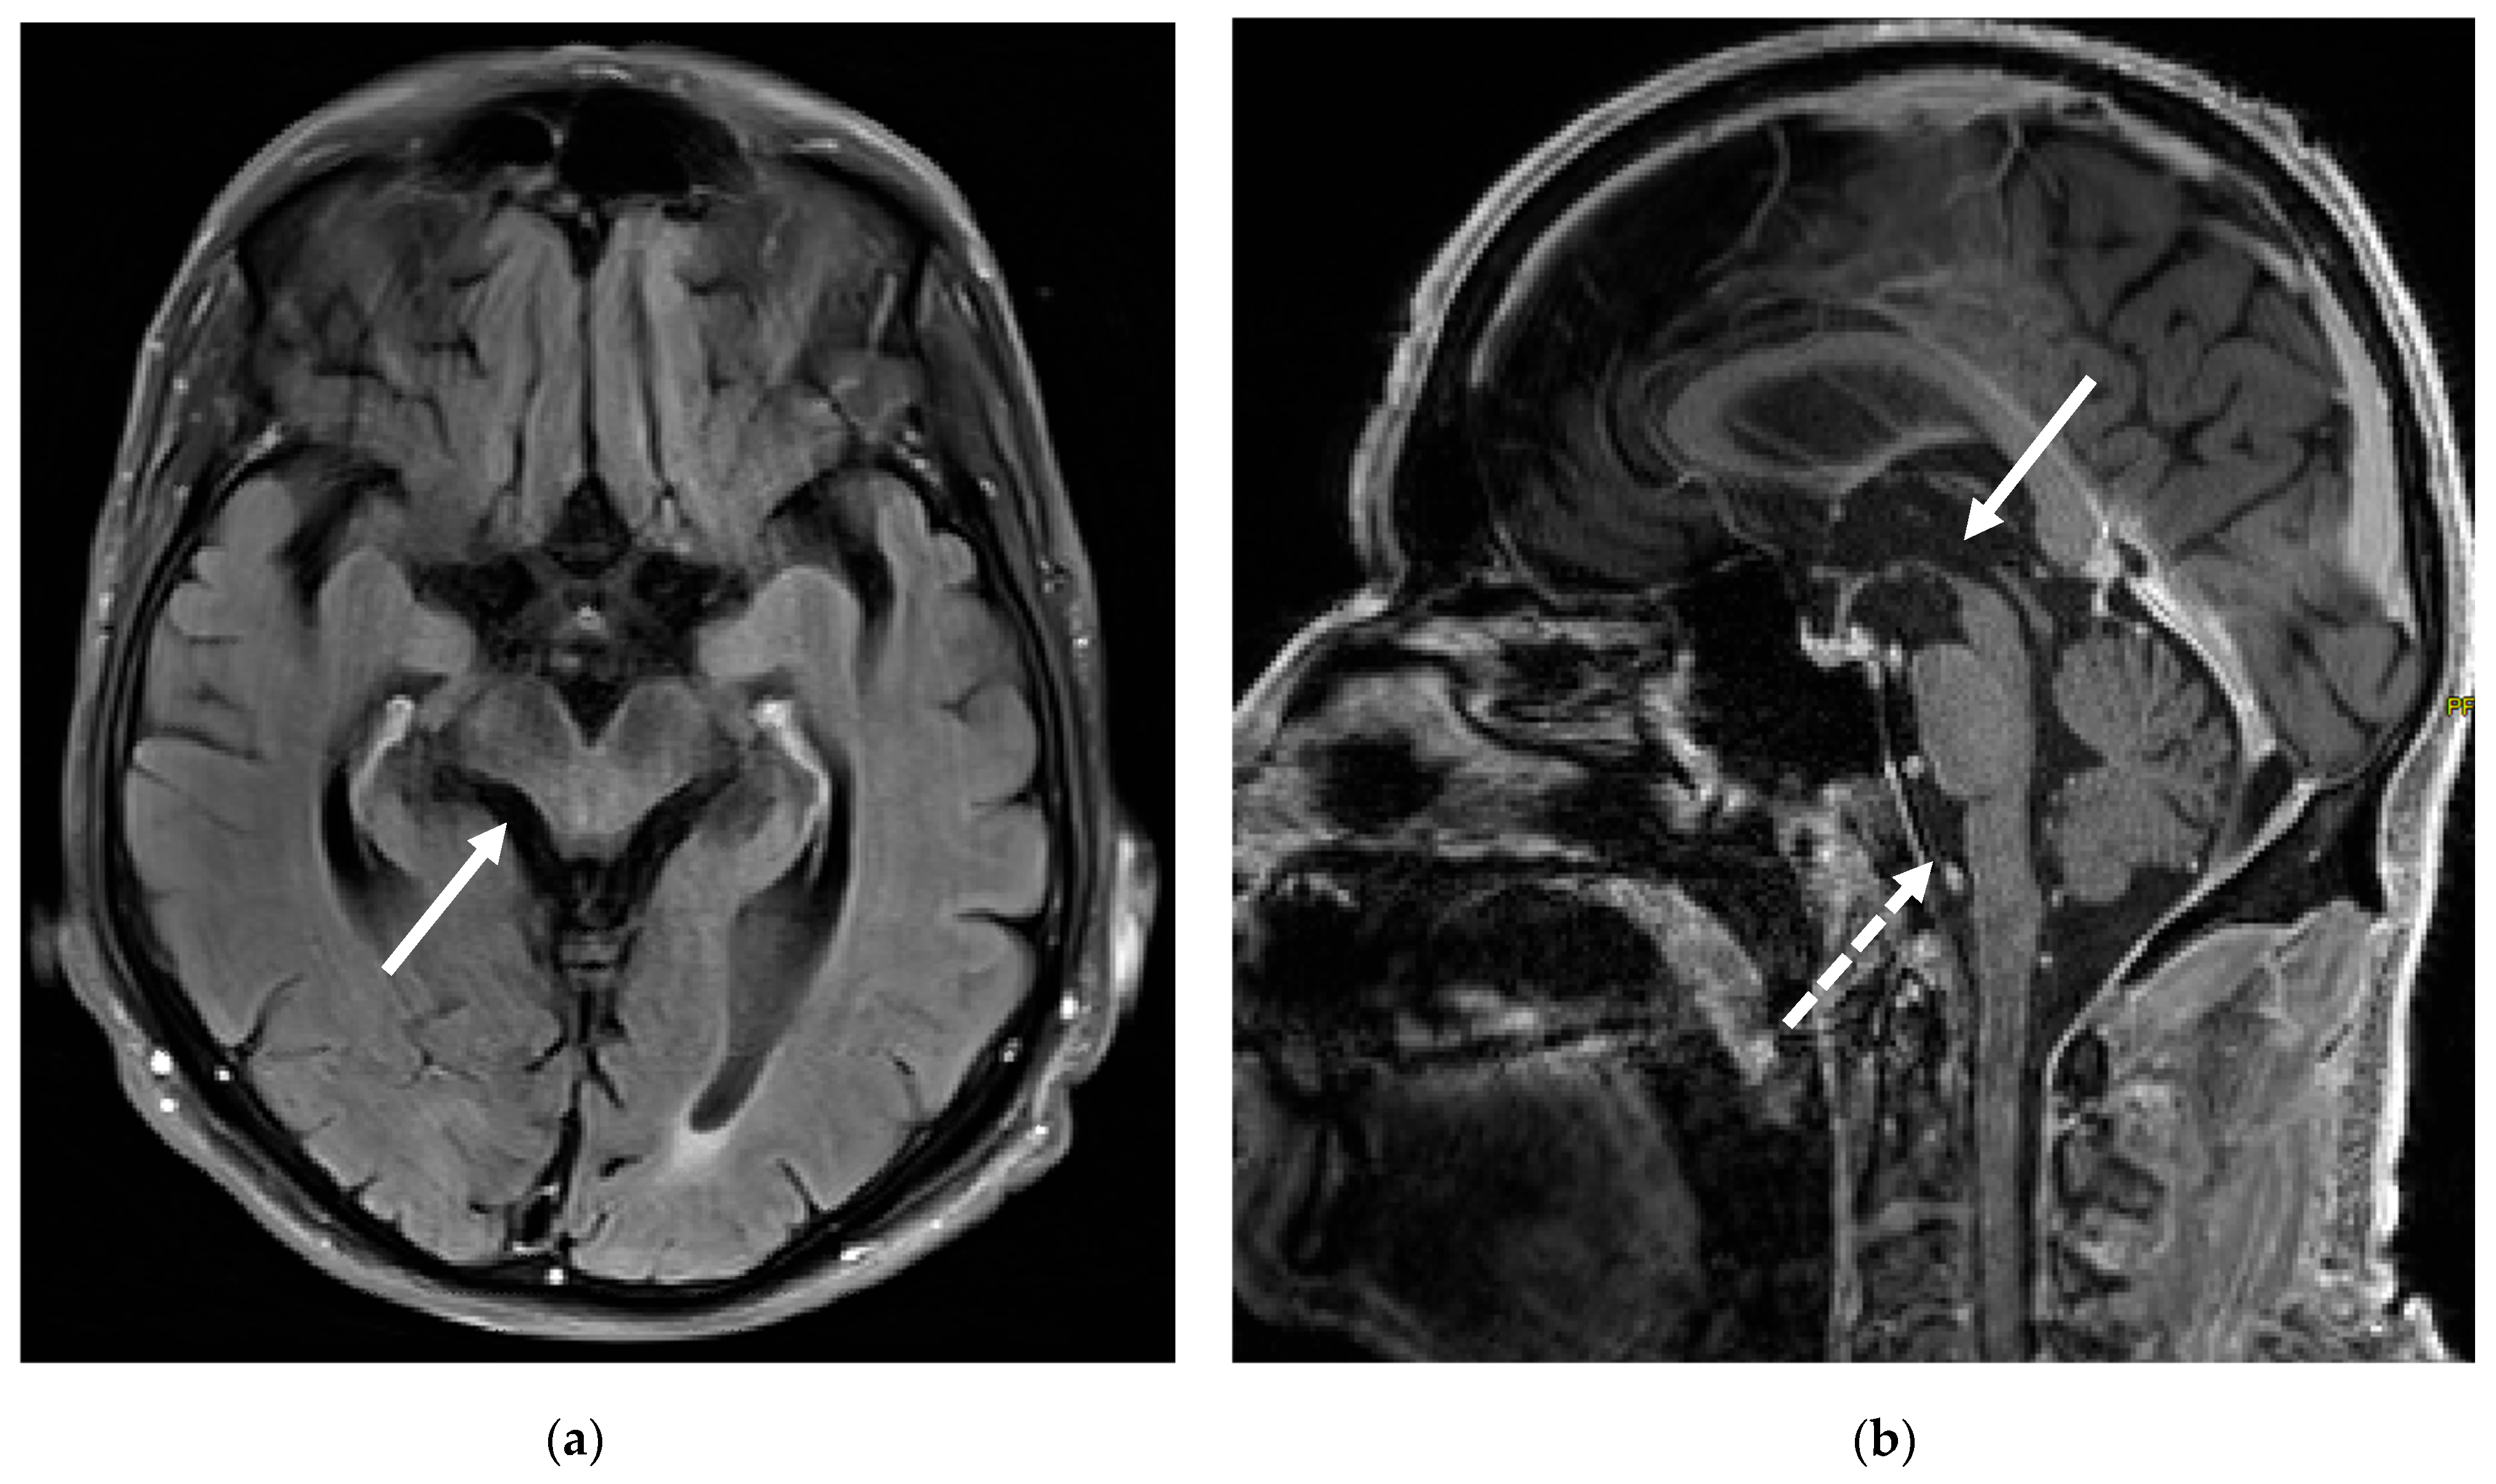

3. Case Report